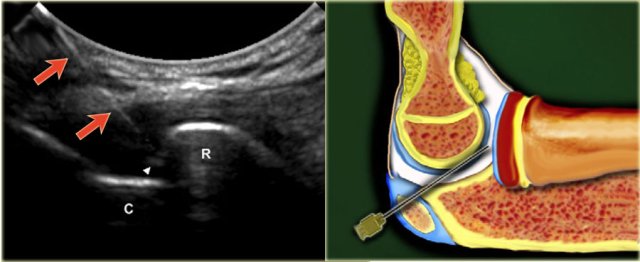

For injection of the ankle (tibiotalar joint) the patient is supine with the foot in slight plantar flexion.

The medial side of the tibiotalar joint is investigated anteriorly with ultrasound to deter- mine a suitable place for injection, at the same time checking for any excessive joint fluid.

We use a small curved array 8 MHz transducer but if preferred one can use an 18-12 MHz linear array transducer. The long axis of the probe is held in a sagittal plane.

Sonogram showing the needle (arrow) and the needle tip (arrowhead) and the injected contrast media in the tibiotalar joint. Sonogram showing the needle (arrow) and the needle tip (arrowhead) and the injected contrast media in the tibiotalar joint.

The needle, usually 22-gauge (length: 30 mm), is introduced in line with the long imaging axis of the transducer on the medial side of the anterior joint space, medial to the anterior tibial ligament, avoiding ligaments and vessels.

One should identify the talar dome and the overhanging anterior tibial lip. The needle is angled caudo-cranially into the joint under the ventral lip of the distal tibia aiming for the articular surface of the distal tibia.

Contact is felt and once again one ensures that the needle tip is free from the tibial cartilage and that the bevel is facing into the joint.

8-10 ml of contrast is injected into the tibiotalar joint and one sees the anterior capsule swells up with the fluid.

There should be no resistance to injection or pain experienced by the patient.